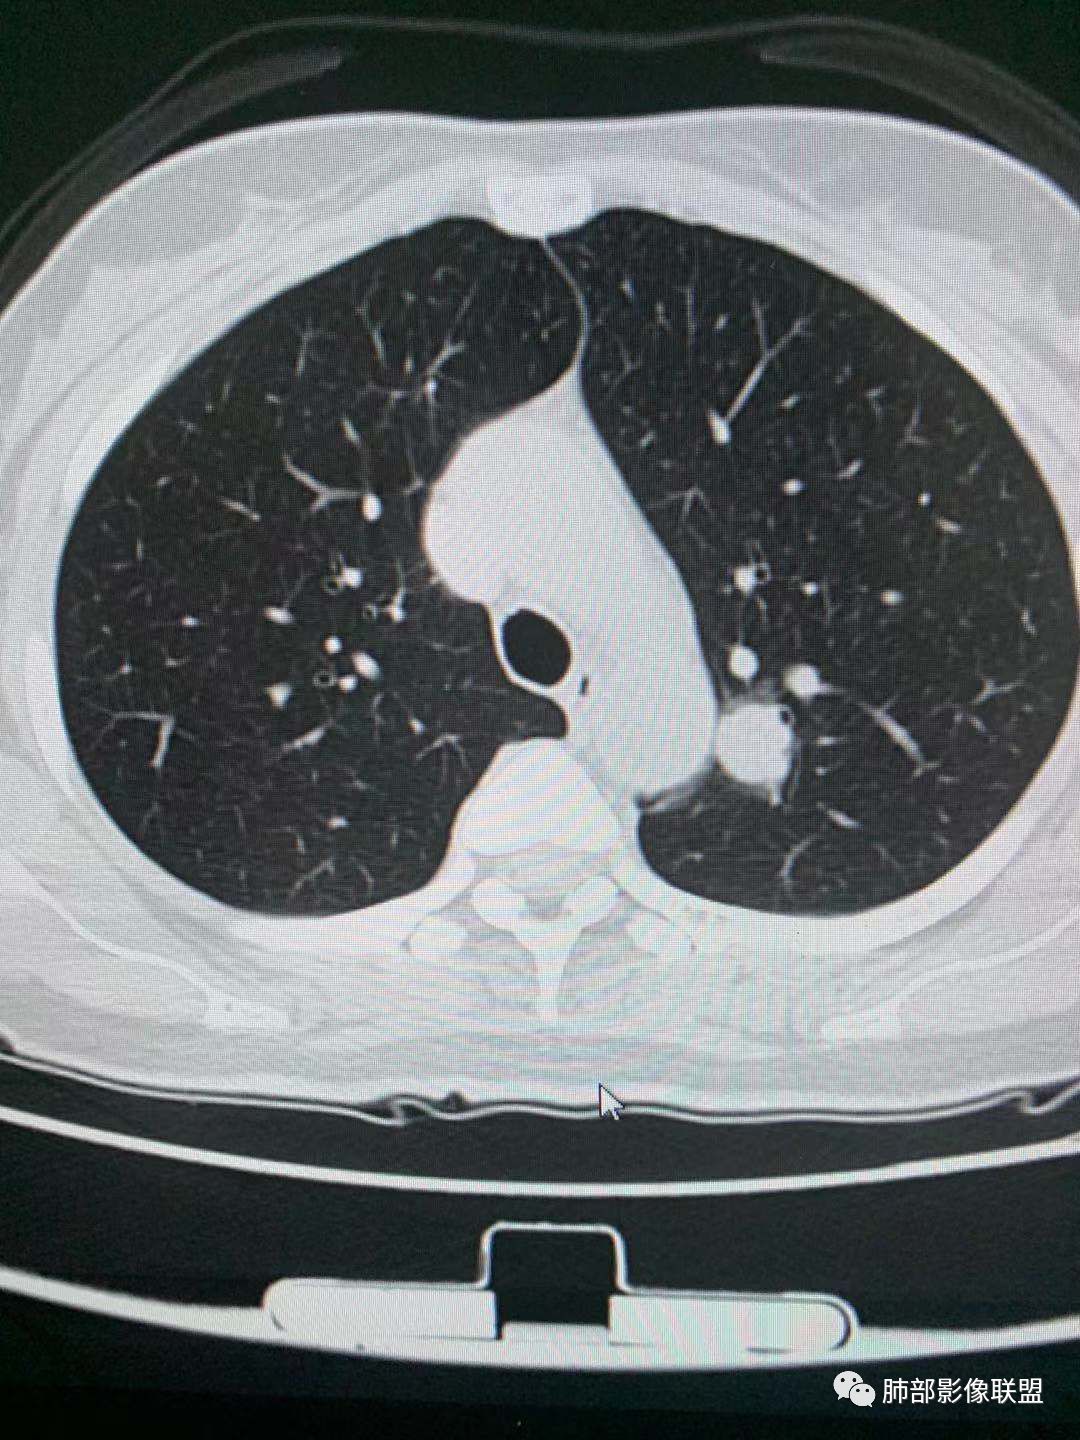

三.右肺上叶胸膜下结节及左肺上叶血管旁结节,尽管都是磨玻璃密度,但都比较小且边缘特征不明显,恶性征象未显露,处置并无特殊,定期复查!

左肺上叶弓旁结节,边缘光滑,支气管血管贴边,延迟强化,周围考虑出血晕,考虑psp,前方两个磨玻璃结节,右肺尖磨玻璃结节,随访观察

左肺上叶尖后段实性结节,周围可见边界清晰ggo,渐进性强化,强化均匀;双上肺多大ggo,一元考虑恶性可能性大,其中左肺尖后段实性结节与psp鉴别

左肺上叶实性结节,光滑,晕,渐进持续强化,血管贴边,尾征,虑psp。另左肺上叶纵膈胸膜下磨玻璃结节收缩力强,胸膜牵拉,考虑腺癌,中带磨玻璃结节细节手机不好看,随访!

一、先讨论GGN吧

1、密度?MGGN?PGGN?

2、边界?清?不清?

3、有无收缩力?有胸膜牵拉?毛刺?

4、血管连通 移动:3型?4型?

两条都进入,相互交通-4

常规判断还需要大小、CT值

大家诊断啥?

二、看第二个结节

1、密度?

2、边界?

3、收缩力?

4、血管?

5、大小、内部结构、CT值

三、看看这一个

1、密度:PGGN?MGGN?